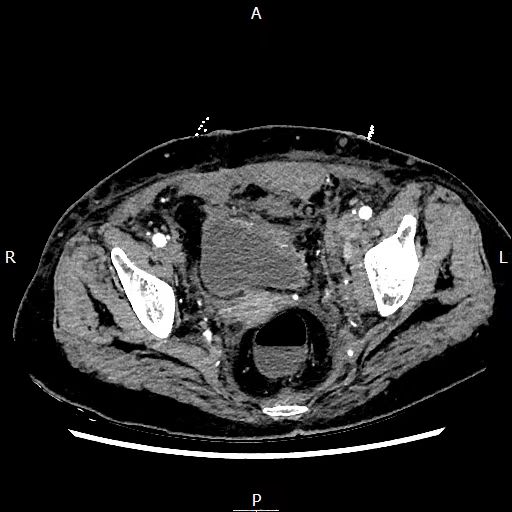

67岁的李婆婆(化名)被送至市一医急诊时,双手紧捂下腹,面色惨白,神志模糊,血压低至79/43mmHg,已处于失血性休克状态。医院立即开启急救绿色通道。急诊医学科医护人员迅速完成初步处置并护送患者完善CT检查,影像显示其腹膜后及盆腔存在广泛积血,预估出血量近2000毫升。

CT提示盆腔巨大血肿